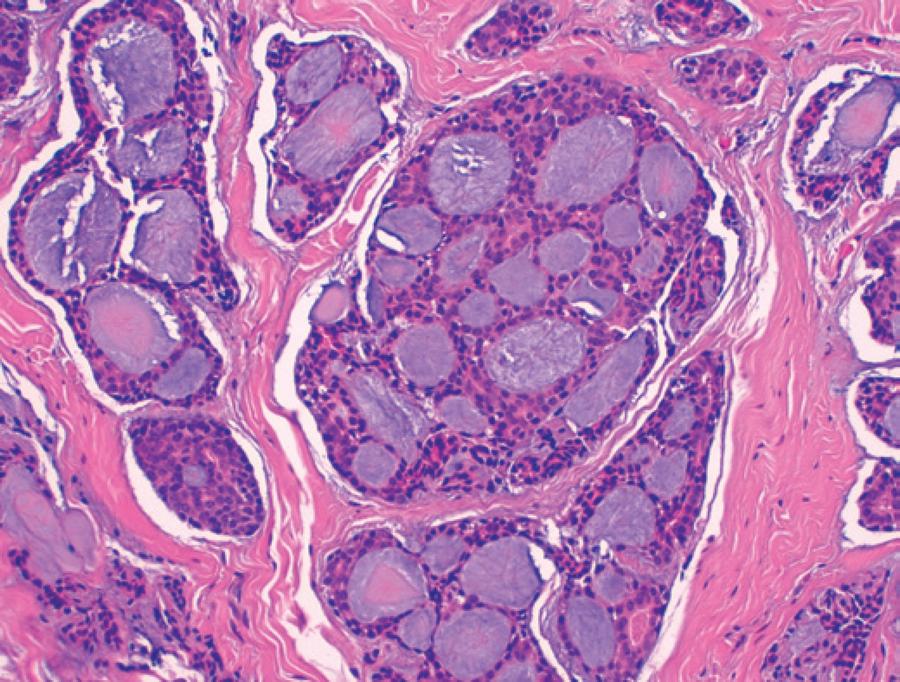

In August 2013, the patient was re-attended complaining of pain in the right canthus and mucosanguineous secretions from the lacrimal punctum in response to pressure. A new DCG was performed demonstrating a filling defect in the sac without passage of contrast into the distal duct. Orbital magnetic resonance imaging identified a solid-cystic lesion measuring 17 × 17 × 13 mm in the right lacrimal sac seen extending towards the orbit and infiltrating the extraconal fatty tissue (Figure 1). Right dacryocystectomy was performed following observation of a gelatinous mass infiltrating the lacrimal sac and eroding the surrounding bony structures. Pathologic examination demonstrated ACC with a predominantly cribriform pattern infiltrating the muscle and bone tissue with additional perineural infiltration (Figure 2). In the extension study, no signs of tumor spread were evident. Further intervention with right lateral rhinotomy located the mass to the canthal area. The tumor planes were dissected and an osteotomy was performed from the canthal ligament to the orbital floor. The orbital floor was reconstructed before tension-free closure and approximation of the rhinotomy flap. Pathological examination of the dissected tissues confirmed the existence of ACC. Following surgery, the patient had a favorable clinical course. A multidisciplinary approach was established, and the patient received 33 sessions of radiotherapy with no signs of recurrence observed after a follow-up for 2 years.

From a histological standpoint, there are three types of ACC: cribriform, tubular, and solid. Cribriform pattern foci are generally constant even when a different histological tumor type predominates. The cribriform pattern is the most common and associated with the best prognosis, whereas the solid type is less frequent but has a poorer prognosis(3,7,8).